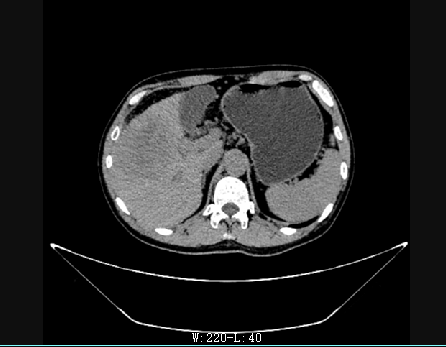

术前

术后